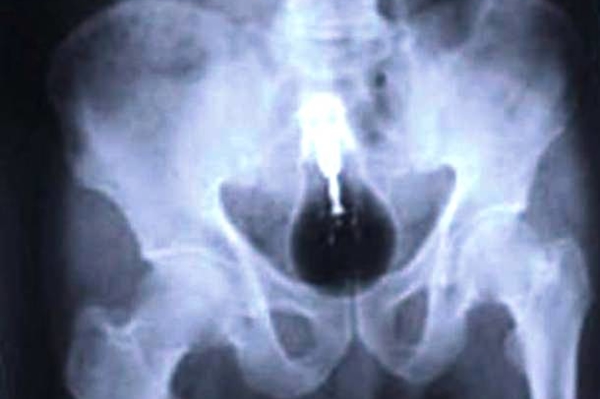

Люди порой поражают медиков странными вкусовыми пристрастиями и удивляют неожиданными вещами, которые по разным причинам оказались в человеческом теле и доступны взору только на рентгеновских снимках. Смотри подборку самых неожиданных находок в человеческом организме

Некоторые люди умудрились удивить медиков странными находками, обнаружившимися в их желудках и телах на рентгеновских снимках. Следует отметить, что многие предметы оказались в человеческом организме волей случая, но некоторые из них - по воле их носителей.